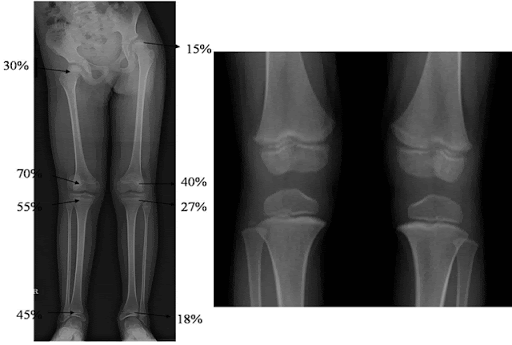

(슬관절에서 길이성장이 많이 일어납니다.)

하지 전체로 보았을 때에는 총 100%라고 보았을 때 대퇴근위15%/대퇴원위40%/경골근위27%/경골원위18% 로

대퇴뼈에서 길이성장을 더 많이 하는 것을 알 수 있습니다.